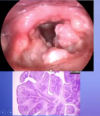

What aspect of the provided images indicate a diagnosis of squamous cell carcinoma

Left: keratin pearl

Right: Intercellular bridges